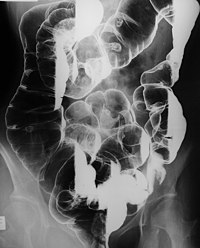

- Π Π΅Π½ΡΠ³Π΅Π½ΠΎΠ³ΡΠ°ΡΠΈΡ ΡΠΎΠ½ΠΊΠΎΠΉ ΠΊΠΈΡΠΊΠΈ — ΠΊΠ°ΠΆΠ΄ΡΠ΅ 2 Π³ΠΎΠ΄Π°,.

Π.β Π. Ρ. ΠΏΡΠΎΡΠ²Π»ΡΠ΅ΡΡΡ ΠΌΠ½ΠΎΠΆΠ΅ΡΡΠ²Π΅Π½Π½ΡΠΌ ΠΏΠΎΠ»ΠΈΠΏΠΎΠ·ΠΎΠΌ ΡΠΎΠ½ΠΊΠΎΠΉ ΠΊΠΈΡΠΊΠΈ, ΡΠ΅ΠΆΠ΅ ΠΏΠΎΡΠ°ΠΆΠ°Π΅ΡΡΡ ΡΠ°ΠΊΠΆΠ΅ ΡΠΎΠ»ΡΡΠ°Ρ ΠΊΠΈΡΠΊΠ° ΠΈ ΠΆΠ΅Π»ΡΠ΄ΠΎΠΊ, ΠΈ ΠΎΡΠ°Π³ΠΎΠ²ΡΠΌ ΠΌΠ΅Π»Π°Π½ΠΎΠ·ΠΎΠΌ (ΡΠΌ.) Π² Π²ΠΈΠ΄Π΅ ΡΠ΅ΠΌΠ½ΡΡ Π²Π΅ΡΠ½ΡΡΠ΅ΠΊ, ΡΠ΅ΠΆΠ΅ ΠΏΡΡΠ΅Π½ ΡΠ²Π΅ΡΠ° ΠΊΠΎΡΠ΅ Ρ ΠΌΠΎΠ»ΠΎΠΊΠΎΠΌ Π½Π° Π³ΡΠ±Π°Ρ (Π²ΠΎΠΊΡΡΠ³ΡΠΎΡΠΎΠ²ΠΎΠ΅ Π»Π΅Π½ΡΠΈΠ³ΠΎ), ΠΊΠΎΠΆΠ΅ Π»ΠΈΡΠ°, ΠΈΠ½ΠΎΠ³Π΄Π° ΡΠ»ΠΈΠ·ΠΈΡΡΠΎΠΉ ΠΎΠ±ΠΎΠ»ΠΎΡΠΊΠ΅ ΠΏΠΎΠ»ΠΎΡΡΠΈ ΡΡΠ° ΠΈ ΠΊΠΎΠΆΠ΅ Π΄ΡΡΠ³ΠΈΡ ΠΎΠ±Π»Π°ΡΡΠ΅ΠΉ ΡΠ΅Π»Π°. ΠΡΠ°Π³ΠΈ ΠΌΠ΅Π»Π°Π½ΠΎΠ·Π° Π²ΡΡΠ²Π»ΡΡΡΡΡ Ρ ΡΠΎΠΆΠ΄Π΅Π½ΠΈΡ ΠΈΠ»ΠΈ Π² ΡΠ°Π½Π½Π΅ΠΌ Π΄Π΅ΡΡΠΊΠΎΠΌ Π²ΠΎΠ·ΡΠ°ΡΡΠ΅, Π² Π½Π΅ΠΊ-ΡΡΡ ΡΠ»ΡΡΠ°ΡΡ ΠΌΠΎΠ³ΡΡ Π² ΠΏΠΎΡΠ»Π΅Π΄ΡΡΡΠ΅ΠΌ ΠΈΡΡΠ΅Π·Π½ΡΡΡ. ΠΠΎΠ»ΠΈΠΏΠΎΠ· ΠΆΠ΅Π».-ΠΊΠΈΡ. ΡΡΠ°ΠΊΡΠ° ΡΠ°ΡΠ΅ Π²ΡΡΠ²Π»ΡΠ΅ΡΡΡ Π² Π²ΠΎΠ·ΡΠ°ΡΡΠ΅ ΠΎΡ 5 Π΄ΠΎ 30 Π»Π΅Ρ. ΠΠΎΠ»ΠΈΠΏΡ Π±ΡΠ²Π°ΡΡ ΠΎΡ 0,1 Π΄ΠΎ 2β3 ΡΠΌ Π² Π΄ΠΈΠ°ΠΌΠ΅ΡΡΠ΅ ΠΈ Π±ΠΎΠ»Π΅Π΅, Π³ΠΈΡΡΠΎΠ»ΠΎΠ³ΠΈΡΠ΅ΡΠΊΠΈ ΠΎΠ½ΠΈ ΠΏΡΠ΅Π΄ΡΡΠ°Π²Π»ΡΡΡ ΡΠΎΠ±ΠΎΠΉ Π°Π΄Π΅Π½ΠΎΠΌΡ Ρ Π²ΠΊΠ»ΡΡΠ΅Π½ΠΈΡΠΌΠΈ ΠΌΠ΅Π»Π°Π½ΠΈΠ½Π°. ΠΠ°Π»ΠΈΠ³Π½ΠΈΠ·Π°ΡΠΈΡ ΠΏΠΎΠ»ΠΈΠΏΠΎΠ² ΠΆΠ΅Π».-ΠΊΠΈΡ. ΡΡΠ°ΠΊΡΠ° ΠΏΡΠΈ Π.β Π. Ρ. Π½Π°Π±Π»ΡΠ΄Π°Π΅ΡΡΡ ΡΠ΅Π΄ΠΊΠΎ.

ΠΠΈΠ°Π³Π½ΠΎΠ· ΡΡΡΠ°Π½Π°Π²Π»ΠΈΠ²Π°ΡΡ Π² ΠΎΡΠ½ΠΎΠ²Π½ΠΎΠΌ Ρ ΠΏΠΎΠΌΠΎΡΡΡ ΡΠ΅Π½ΡΠ³Π΅Π½ΠΎΠ»ΠΎΠ³ΠΈΡΠ΅ΡΠΊΠΎΠ³ΠΎ ΠΈ ΡΠ½Π΄ΠΎΡΠΊΠΎΠΏΠΈΡΠ΅ΡΠΊΠΎΠ³ΠΎ ΠΈΡΡΠ»Π΅Π΄ΠΎΠ²Π°Π½ΠΈΠΉ ΠΆΠ΅Π».-ΠΊΠΈΡ. ΡΡΠ°ΠΊΡΠ°. ΠΠ»ΠΈΠ½, ΠΎΠ±ΡΠ»Π΅Π΄ΠΎΠ²Π°Π½ΠΈΠ΅ ΡΠΎΠ΄ΡΡΠ²Π΅Π½Π½ΠΈΠΊΠΎΠ² Π±ΠΎΠ»ΡΠ½ΠΎΠ³ΠΎ ΠΏΠΎΠ·Π²ΠΎΠ»ΡΠ΅Ρ Π²ΡΡΠ²ΠΈΡΡ Π±Π΅ΡΡΠΈΠΌΠΏΡΠΎΠΌΠ½ΠΎ ΠΏΡΠΎΡΠ΅ΠΊΠ°ΡΡΠΈΠ΅ ΡΠ»ΡΡΠ°ΠΈ Π.β Π. Ρ. ΠΠΈΡΡΠ΅ΡΠ΅Π½ΡΠΈΠ°Π»ΡΠ½ΡΠΉ Π΄ΠΈΠ°Π³Π½ΠΎΠ· ΠΏΡΠΎΠ²ΠΎΠ΄ΡΡ Π° Π³Π΅Π½Π΅ΡΠ°Π»ΠΈΠ·ΠΎΠ²Π°Π½Π½ΡΠΌ Π½Π°ΡΠ»Π΅Π΄ΡΡΠ²Π΅Π½Π½ΡΠΌ ΠΏΠΎΠ»ΠΈΠΏΠΎΠ·ΠΎΠΌ, ΡΠΈΠ½Π΄ΡΠΎΠΌΠΎΠΌ ΠΠ°ΡΠ΄Π½Π΅ΡΠ° (ΡΠΌ. ΠΠ°ΡΠ΄Π½Π΅ΡΠ° ΡΠΈΠ½Π΄ΡΠΎΠΌ) ΠΈ Π΄ΡΡΠ³ΠΈΠΌΠΈ ΡΠΎΡΠΌΠ°ΠΌΠΈ Π½Π°ΡΠ»Π΅Π΄ΡΡΠ²Π΅Π½Π½ΠΎΠ³ΠΎ ΠΈ ΠΏΡΠΈΠΎΠ±ΡΠ΅ΡΠ΅Π½Π½ΠΎΠ³ΠΎ ΠΏΠΎΠ»ΠΈΠΏΠΎΠ·Π° ΠΆΠ΅Π».-ΠΊΠΈΡ. ΡΡΠ°ΠΊΡΠ° (ΡΠΌ. ΠΠΈΡΠ΅ΡΠ½ΠΈΠΊ).